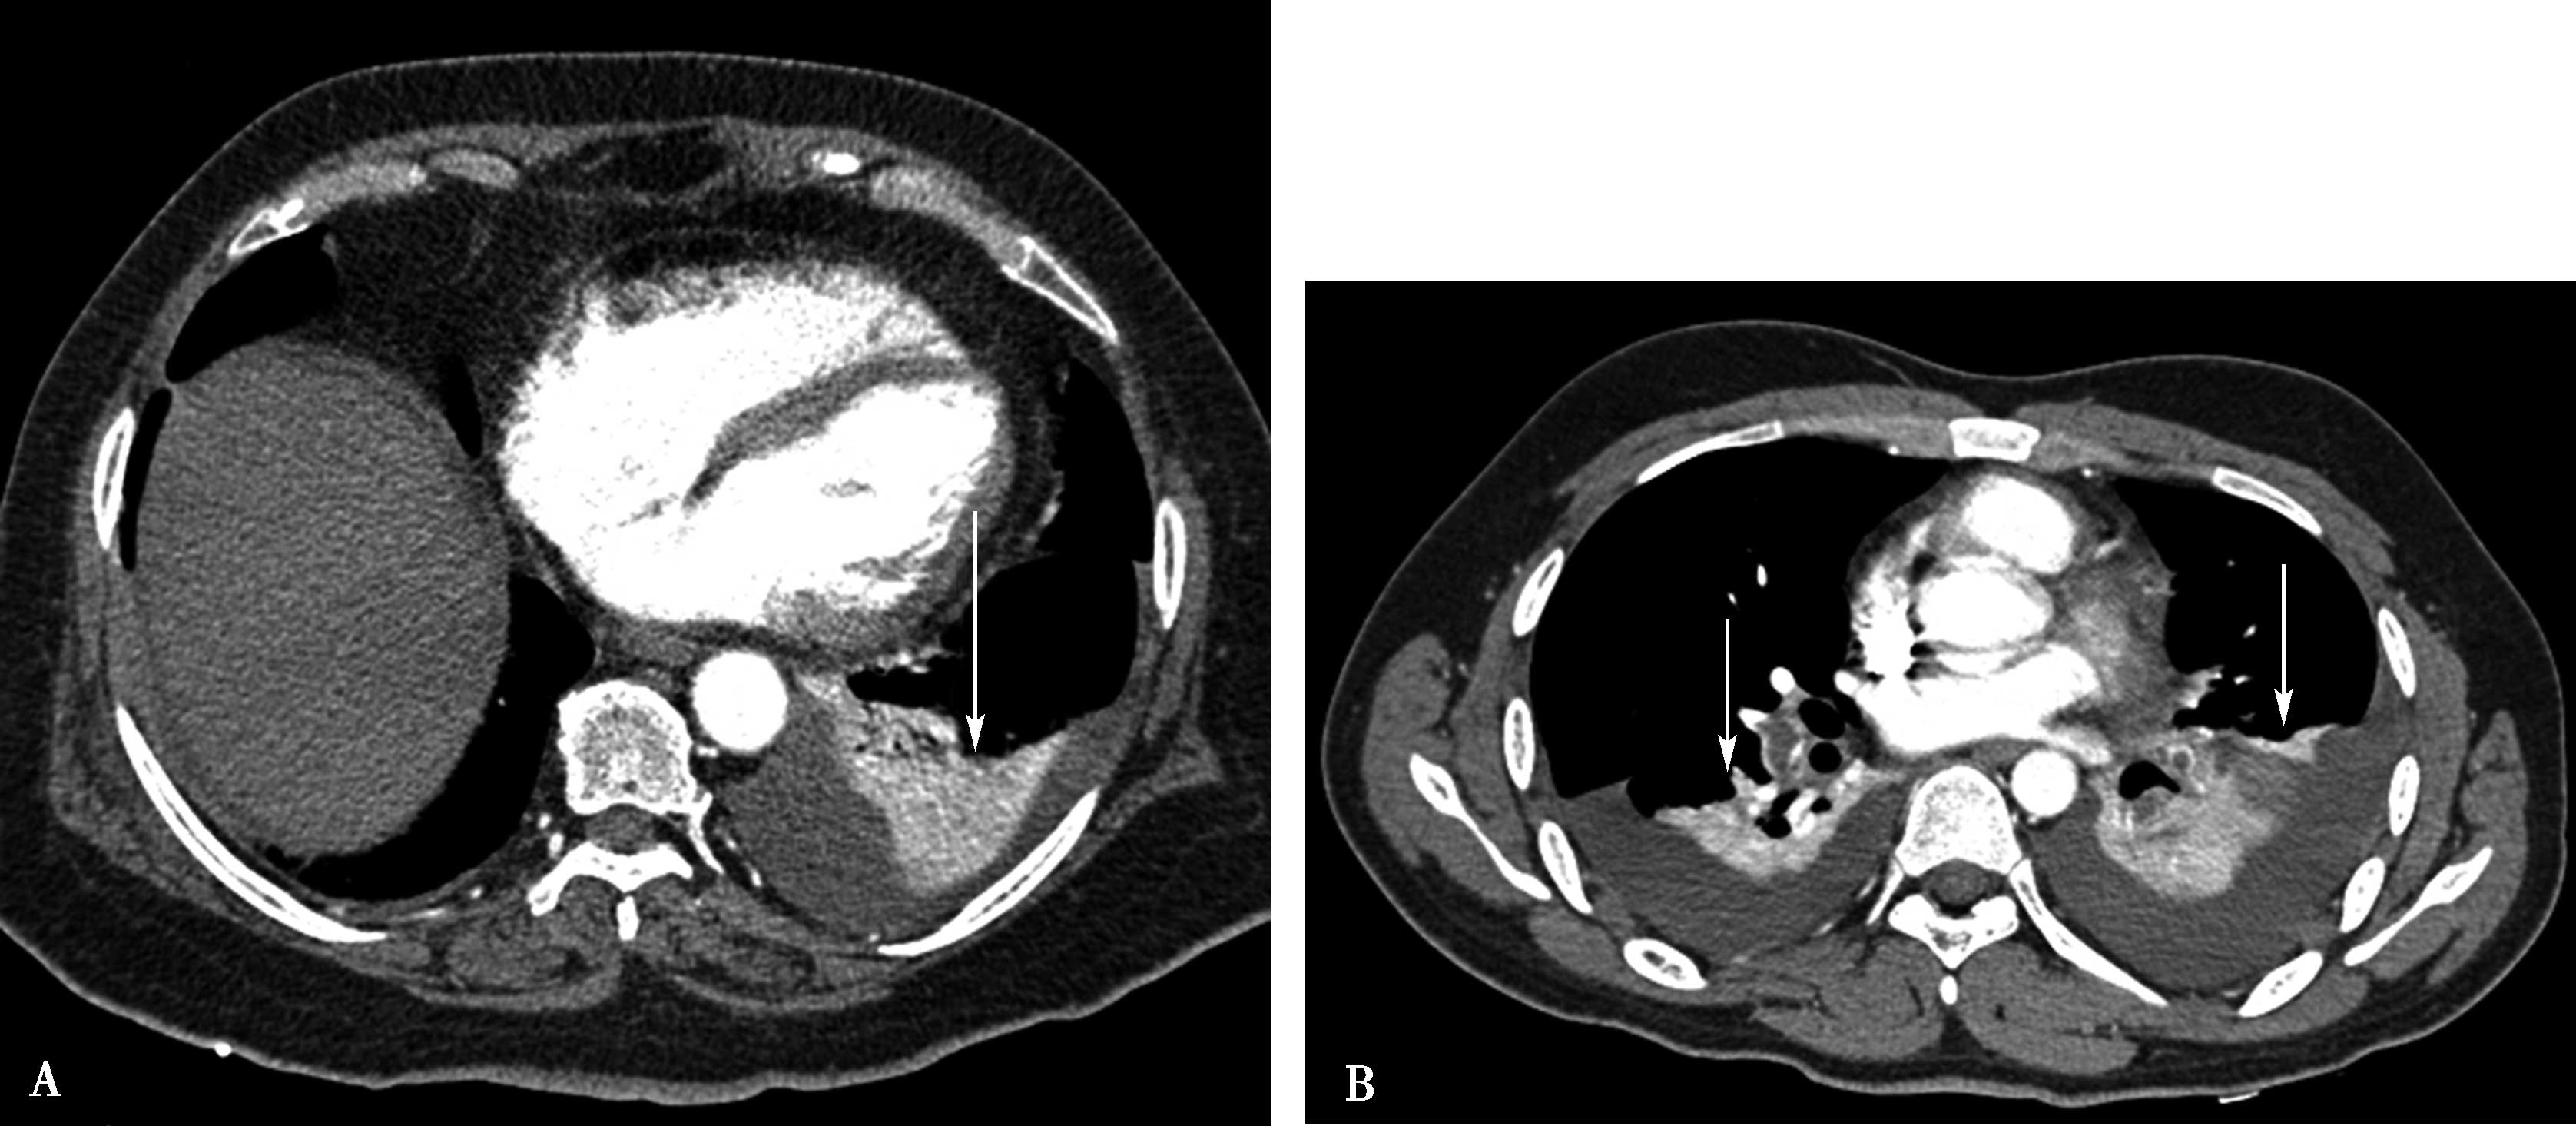

图8-6-1 缩窄性心包炎、纵隔炎(结核性),心包缩窄术后

A、B.横断图像,右肺动脉被纵隔纤维化包围重度狭窄-闭塞(A↑);右侧肺血少(B↑),左侧肺血多(B↑);肺动脉高压,右心房扩大。AO:升主动脉;PA:肺动脉;RPA:右肺动脉;LPA:左肺动脉